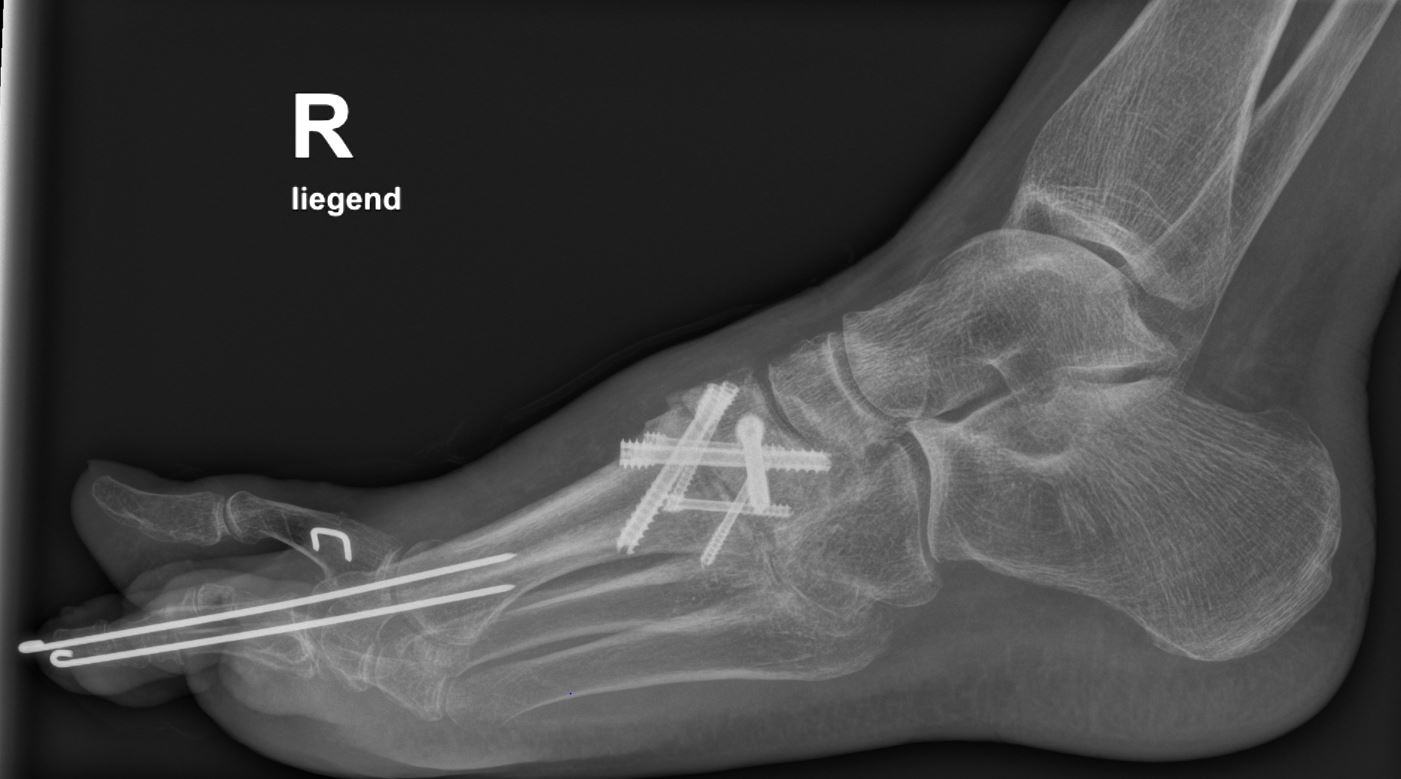

• Röntgenkontrolle nach 8-10 Wochen, dann - je nach knöchernem Durchbau - Übergang zur Vollbelastung im Konfektionsschuh (Abb. 24 und 25).

Beispiel Lisfranc Arthrodese bei posttraumatischer Arthrose

Zum Lesen der Bildbeschreibung und zur Vollansicht bitte die Bilder anklicken. Bilder: C. Hase